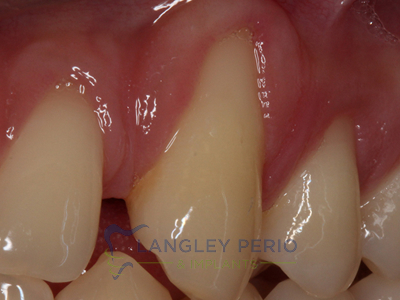

Case 2

Connective tissue grafting was done to cover exposed root surfaces to help to prevent root cavities from developing and reduce temperature sensitivity.